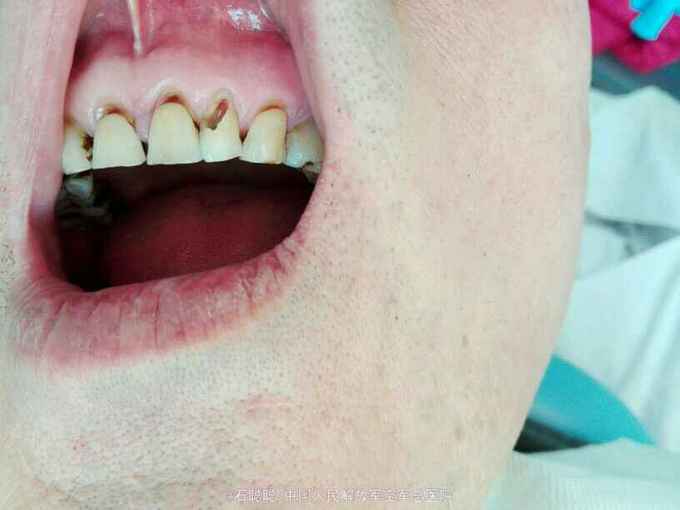

检查:左上234唇侧牙龈红肿,轻压见左上23治疗窦道口溢脓,肿胀区扪诊疼痛,左上2根尖区疼痛最为明显,左上2松动1-2度,叩痛++,唇侧树脂充填 根尖片:左上2根尖区见类圆形直径约1cm的低密度透射影,边界模糊

诊断:左上2根尖周脓肿 治疗计划:开髓引流,消炎镇痛,后期根管治疗 处置:左上2去旧充填物,见树脂充填物进去髓腔,探及根管口,疏通,见大量脓性,血性液体渗出,开放,口服头孢、甲硝唑 次日复诊: 诉肿胀疼痛减轻 查:左上234唇侧牙龈肿胀减轻,扪诊疼痛减轻,左上2松动度减轻 处:进一步疏通扩大至25#,见混浊血性渗出,继续开放 次日复诊:左上234唇侧牙龈肿胀消退,叩痛消失,松动度明显减小,冲洗,干燥,封CP棉球,告知患者一周后复诊,继续完成治疗